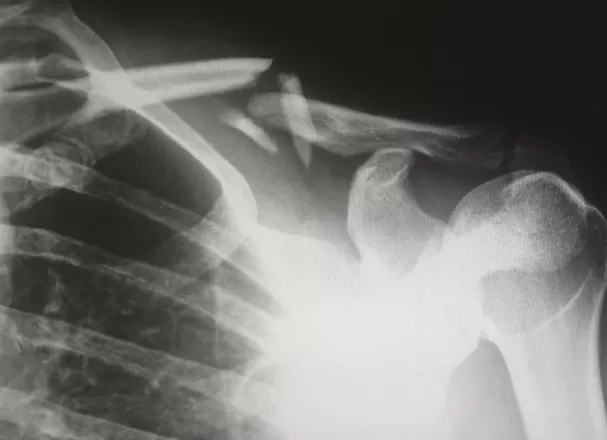

Erleidet jemand einen Skiunfall und fällt mit gebrochener Schulter für eine gewisse Zeit aus, werden zusätzliche Behandlungen wie etwa der Spitalaufenthalt, die Operation oder auch ein Teil des Lohnausfalls übernommen. Schwerwiegende Unfälle, die dazu führen, dass die verunfallte Person invalide wird, lassen zudem den Anspruch auf eine entsprechende lebenslange Invalidenrente entstehen, die von der IV und zusätzlich von der Unfallversicherung nach UVG ausbezahlt wird. Im schlimmsten Fall, nämlich bei einem Todesfall aufgrund eines Unfallereignisses, erhalten die Hinterbliebenen unter Umständen Hinterlassenenrenten. Es mag zwar etwas makaber klingen, aber: Stirbt eine versicherte Person bei einem Unfall, übernimmt der Unfallversicherer sogar einen Teil der Bestattungskosten.